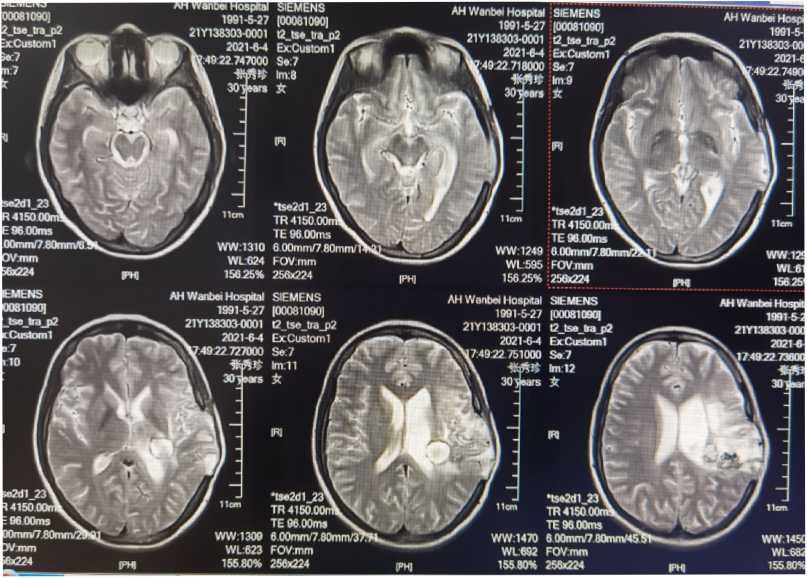

病情稳定后行MRI检查

可以见血管流空影,AVM